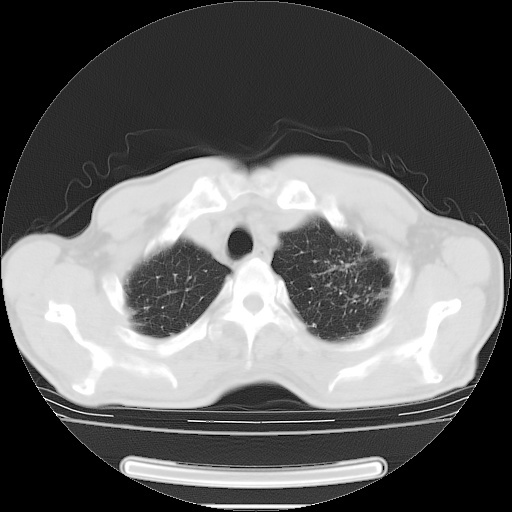

男性患者,63岁。右侧胸背部疼痛2月,加重一周。

考虑:右肺中央型肺癌并右肺下叶不张;两肺尖继发性肺结核。

右肺下叶支气管狭窄闭塞,右下肺不张,气管前间隙淋巴结肿大,两上肺散在分部粟粒灶,沿肺血管支气管束分部,血管支气管束走形较为光滑。考虑右肺中心型肺癌合并肺不张,纵隔淋巴结转移,两上肺癌性淋巴管炎

右肺下叶中心性肺癌并纵隔淋巴结转移,左侧肋骨转移。双肺上叶继发性结核表现。

1)右肺下叶中心性肺癌并纵隔淋巴结转移,两肺转移,左侧肋骨转移。2)双肺上叶继发性结核。

右肺下叶中心性肺癌并纵隔淋巴结及两肺、左侧肋骨转移。双肺上叶继发性结核表现。